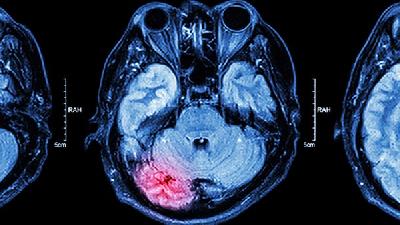

酒精性脑萎缩症状有什么呢?酒精性脑萎缩顾名思义就是由于饮酒造成的脑细胞萎缩的一种脑部疾病,所以长期饮酒的中老年朋友尤其需要注意。详解酒精性脑萎缩症状下面就请专家为我们详细讲讲酒精性脑萎缩症状。

脑萎缩多见于有长期大量饮酒史的男性,一般均有慢性酒精中毒的表现。多见于中老年人。酒精性脑萎缩症状有:发病隐袭,且逐渐缓慢进展。有些患者可合并周围神经病变和肌肉萎缩,甚至出现震颤、幻觉。妄想癫痫大发作等严重酒精中毒的表现。头颅CT示脑沟增宽、脑回变小、脑池和脑室扩大等酒精性脑萎缩症状。

酒精性脑萎缩症状是早期常有焦虑不安、头痛、失眠、乏力等,逐渐出现智力衰退和人格改变除非有严重脑萎缩,一般无明显痴呆。可较长时期保持良好的工作能力。详解酒精性脑萎缩症状患者主诉有明显的记忆力减退,并可有计算力、判断和分析能力下降。少数可出现遗忘、虚构和定向障碍的Korsakoff精神病表现。人格改变可有自私、生活散漫、情绪不稳、易激惹、工作效率低、缺乏责任感、不听人劝告和人际关系紧张等。严重者酒精性脑萎缩症状有智能衰退和智商明显下降。